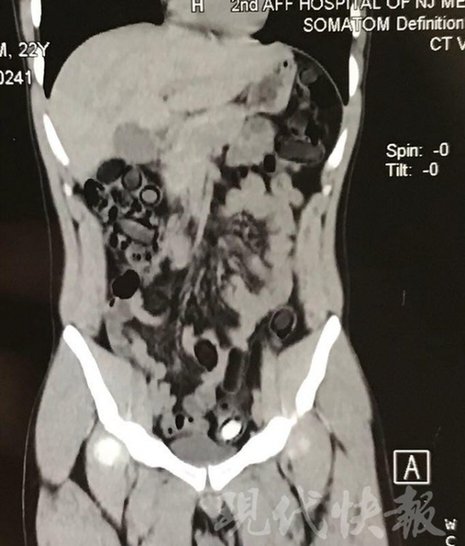

小伙體內(nèi)藏毒300余克 CT掃描圖密密麻麻

由于毒品在體內(nèi)一旦泄露有可能致命,警方第一時(shí)間將阿永帶到醫(yī)院進(jìn)行檢查。CT 掃描的結(jié)果顯示,阿永體內(nèi)布滿(mǎn)了密密麻麻的白色圓柱狀固體,就像一粒粒的蠶蛹。在南京市公安局鼓樓分局二板橋派出所,阿永分四次排出了毒品,毛重369.99克。經(jīng)訊問(wèn),阿永交代了自己全部的犯罪事實(shí)。目前,阿永已被刑事拘留。